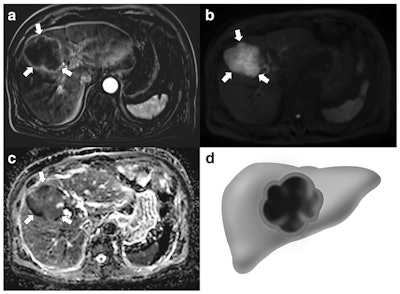

A 76-year-old man with gallbladder adenocarcinoma. A: Subtraction images taken during the arterial phase of an axial contrast-enhanced MRI show a 7.5-cm mass replacing the gallbladder with thin peripheral rim enhancement (arrows). On diffusion-weighted imaging (B) and apparent diffusion coefficient mapping (C), this mass demonstrates a nonthick rim appearance (arrows). Extended right lobectomy was performed, and a poorly differentiated adenocarcinoma was histopathologically confirmed. D: Nonthick rim appearance."We found that GB-NETs were significantly larger, frequently had a well-defined margin and intact overlying mucosa, and more often showed thick rim contrast enhancement and diffusion restriction, compared with GB-ADCs," the authors wrote. "In addition, liver and lymph node metastases were more common for GB-NETs, and these also demonstrated thick rim contrast enhancement and diffusion restriction."